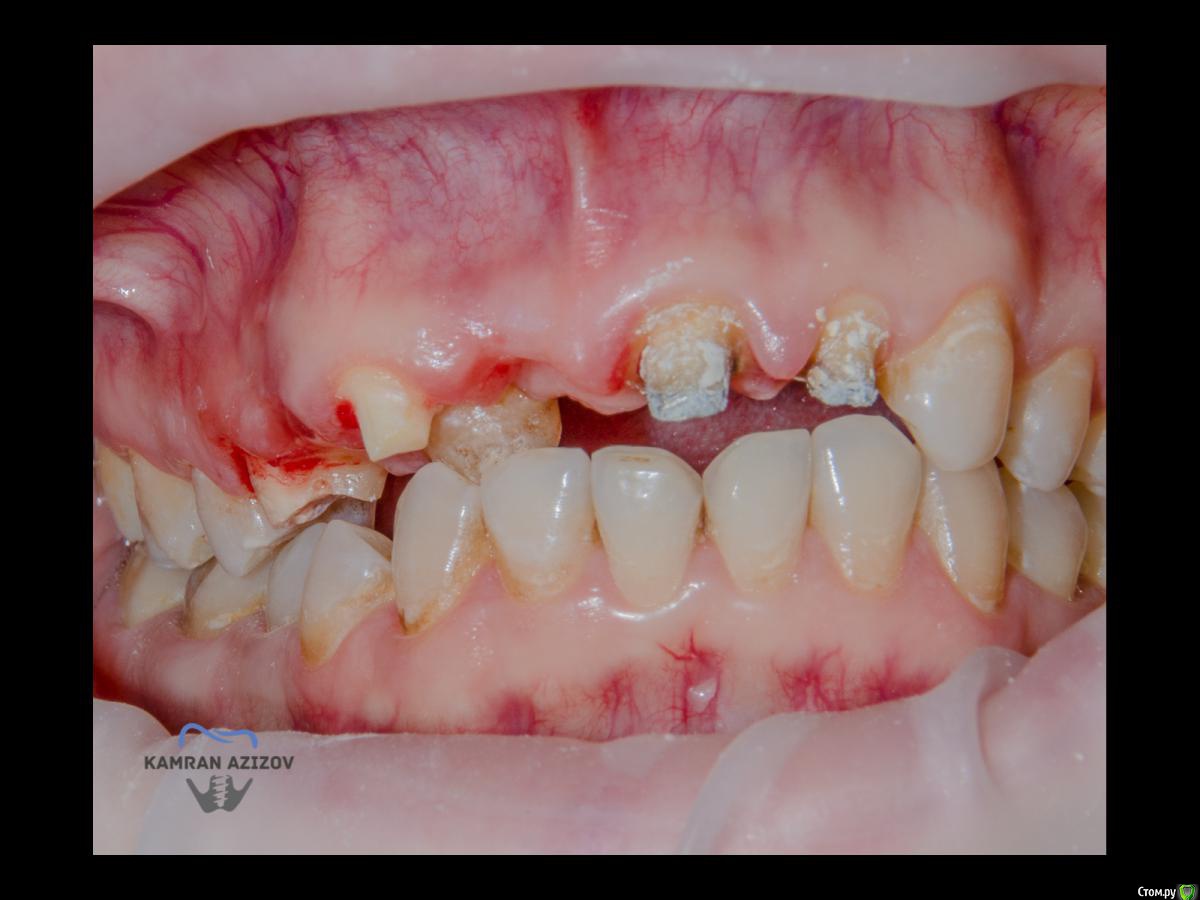

kamranchick Опубликовано 6 апреля, 2019 Поделиться Опубликовано 6 апреля, 2019 (изменено) Хай Гайсдавно ничего не комментировал и не выкладывал, что то настроения не было, да и муза не посещалаСитуация следующаяпришла пациентка, жалобы на неприятный запах из рта, сначала не понял что за хрень, ну как распилил мост понял че к чему... халтура.Ну и по кейсуУдаление клыка и 2ки, через 2 месяца навигация, имплантация + Шашлыки по карлоссу, смена формиков, временное протезирование. только мягкие ткани, Изменено 6 апреля, 2019 пользователем kamranchick 7 1 Ссылка на комментарий

АнтонТЛТ Опубликовано 6 апреля, 2019 Поделиться Опубликовано 6 апреля, 2019 Чё то двойку слишком небно запилил 2 Ссылка на комментарий

kamranchick Опубликовано 6 апреля, 2019 Автор Поделиться Опубликовано 6 апреля, 2019 Ориентировались тут в основном по кости... Ссылка на комментарий